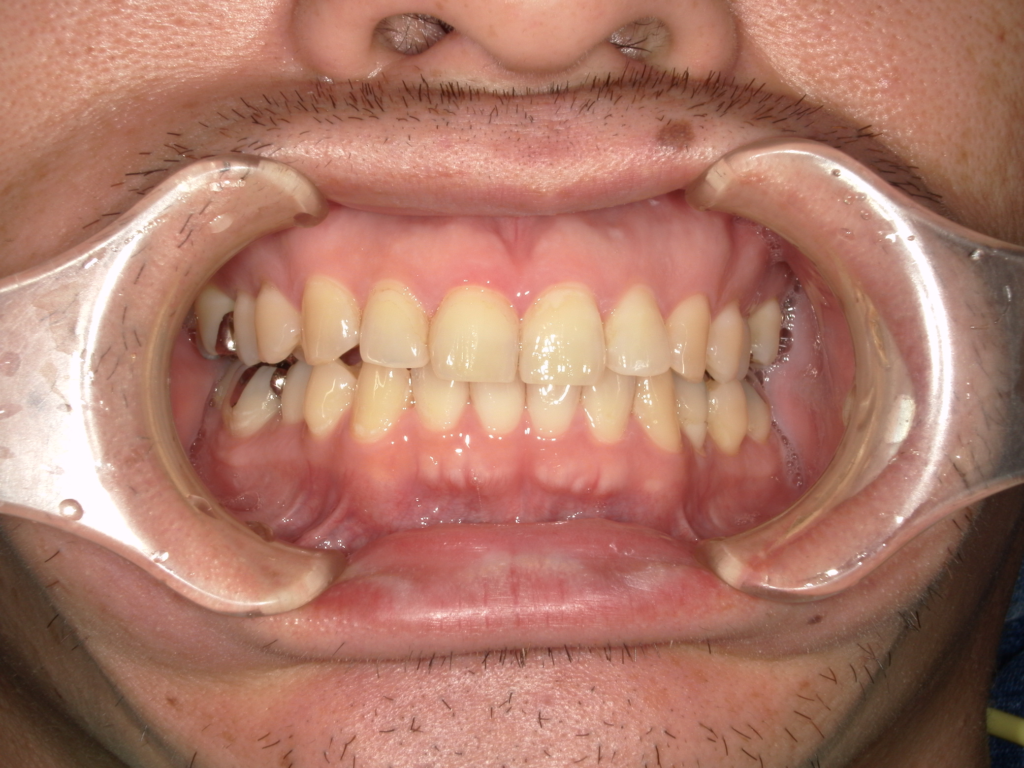

K様 インプラント実例 #25

上の前歯4本をインプラント治療で治しています。前歯4本を抜歯して、真ん中の歯に2本インプラントを埋入しています。抜歯したと同時に仮歯(前歯4本)を作りました。最終な上部構造物は、セラミックスで仕上げています

治療前

治療後